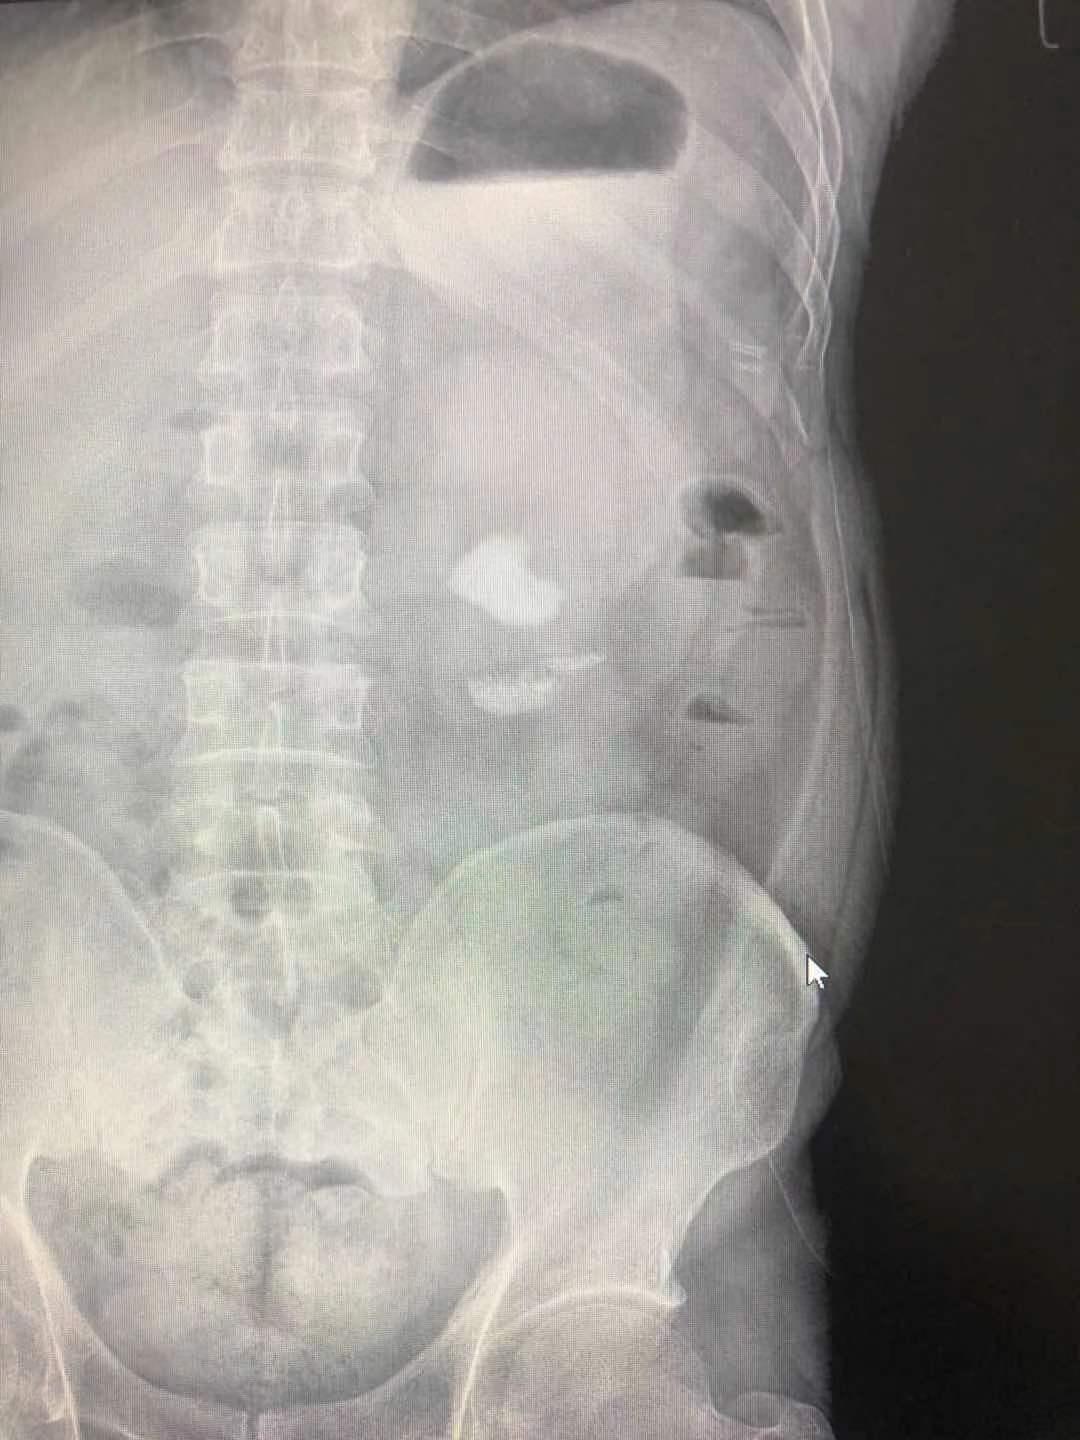

患者,男,40岁,以“间断性左侧腰腹部酸疼不适1月半”,入住我院泌尿外科。患者1月半前无明显诱因,出现左侧腰腹部间断性轻度酸疼不适,无恶心反胃,无寒战、发热,无咳嗽、咳痰,无尿频、尿急、尿痛,无肉眼血尿,3天前在利辛县某医院查腹部CT显示:左肾多发结石伴肾积水,最大结石约31mmX18mm,其就诊医生告诉患者其结石较大,需到省级以上医院就诊。患者经多方打听到我院可以治疗较大肾结石,遂来我院就诊。门诊医师以“左肾结石”收住入院。

入院后泌尿外科张国田主任仔细阅读患者泌尿系CT,诊断患者为左肾铸形结石合并肾盏结石,经过科室讨论,决定行“经皮肾镜左肾结石碎石取石术”。

积极术前准备,由手术室配合在全麻下行“经皮肾镜左肾结石碎石取石术”,手术历时约一个小时完成,不仅击碎并取净了肾盂内的铸形结石,连肾盏内的结石也一并击碎取出,术后患者恢复良好,于1周后出院,为表示感谢,特地送来一面锦旗。